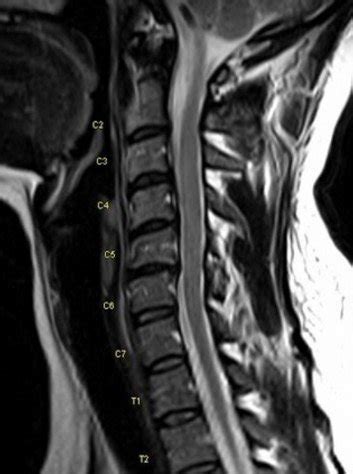

Magnetic resonance image. Radiology reported noted generalized disc ...

AMICUS Illustration of amicus,injury,injuries,cervical,spine,MRI ...